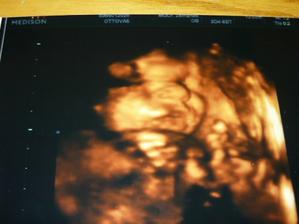

5/1/09 : 3D UTZ, opět potvrzena holčička, vážíme 510g. a měříme 25 cm.